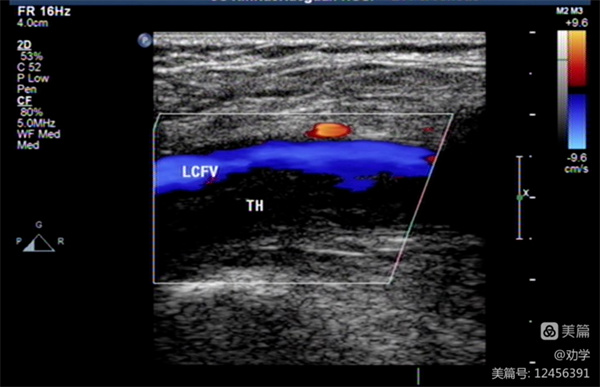

静脉血栓栓塞症是血液在静脉内不正常的凝结,使血管完全或不完全阻塞,属于静脉回流障碍性疾病。静脉血栓栓塞症包括深静脉血栓(DVT)和肺动脉栓塞(PTE),两者互相关联,是静脉血栓栓塞症在不同部位和不同阶段的两种临床表现形式。静脉血栓形成与肺栓塞是一个疾病的两个不同阶段。在我国长期以来, 绝大多数肺动脉栓塞被误诊、漏诊,是猝死的重要原因之一。

大部分深静脉血栓形成具有隐匿性,并无明显症状,少数患者可发生有症状性的深静脉血栓,可表现为如下症状中的一种或者多种:患肢体突然肿胀、发硬、疼痛、触觉异常(活动后加重,抬高患肢可减轻,静脉血栓部位常伴压痛)下肢单侧(或双侧,多为左下肢)、臀部、下腹或外生殖器水肿皮温升高等。肺栓塞的症状则为:不明原因的气促、呼吸困难、胸痛、心悸及晕厥等。